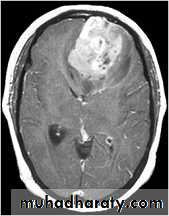

Glioma

Comments primary interracial tumor , vary greatly in malignancy , have many names depending on the histological type :

astrocytoma

oligodendroglioma both of them are well differentiated slowly growing t.

gliobtastoma multiforme G IV highly malignant t. named also as butterfly G. arise from the anterior or posterior aspect of the corpus callosum , extend & spread to both cerebral hemispheric sides

grading of malignancy of G. depending on the following :

well defined or irregularity of the lesion

surrounding edema present or absent

associated shifting of midline & crossed midline lesion

contrast enhancement

associated hemorrhage , necrosis , & cystic formation

seeding via csf & dissemination .

Low grade G. I well or ill defined lesion iso dence to the brain tissues , not associated with oedeme , no Enhancement , no associated Hemorrhage , necrosis .

From G II , III, various previous finding

IV( glioblastoma multiforme ) are highly malignant have all previous mentioned features .